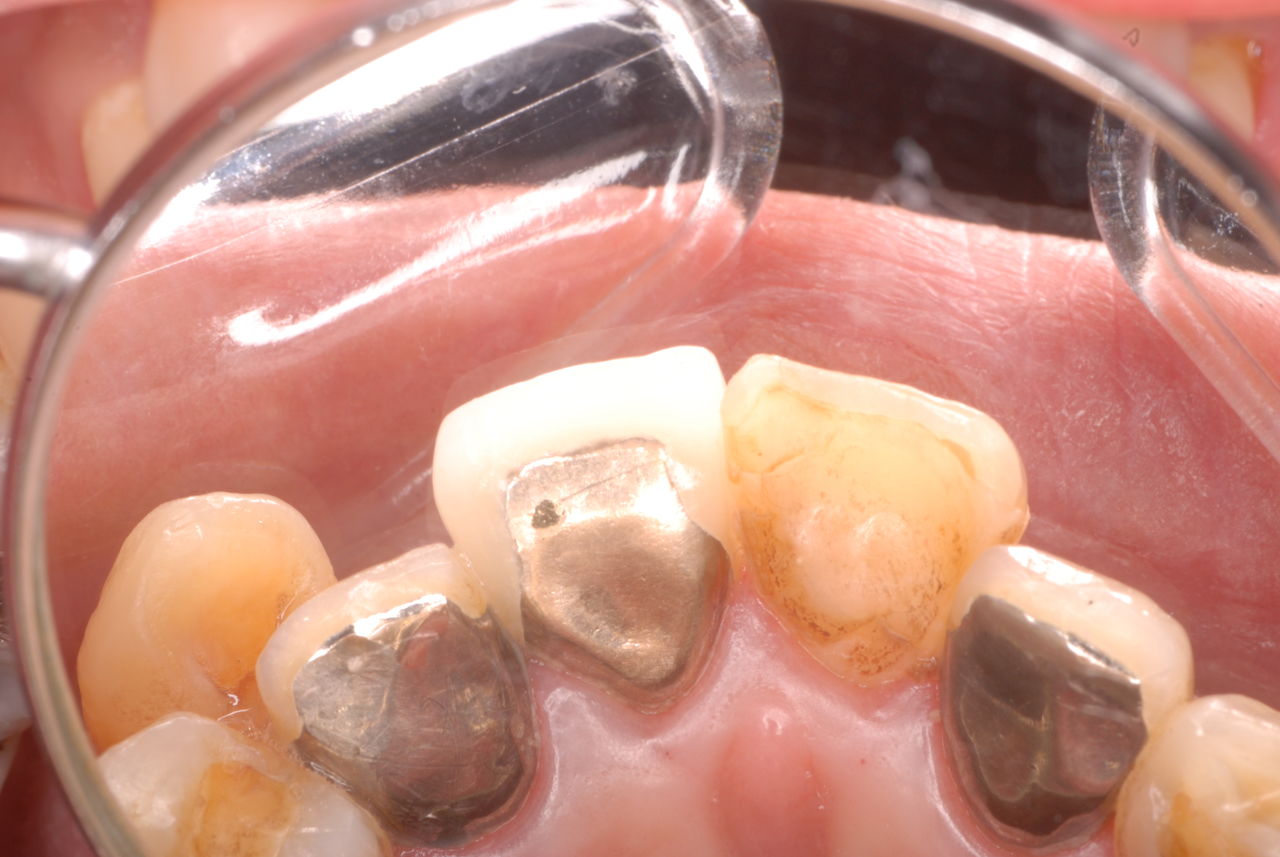

歯周病の疑いで東京のかなり遠方の方が来院されました。

驚くべきことですが、定期検診は受けていたそうです。しかしながら歯周病の指摘は受けたことがないそうです。

何故か?定期検診が虫歯のチェックのみになり、又肝心の歯周病の検査や歯周病の部分の予防や治療のためのブラシの使い方などを学んだ事がないのです。